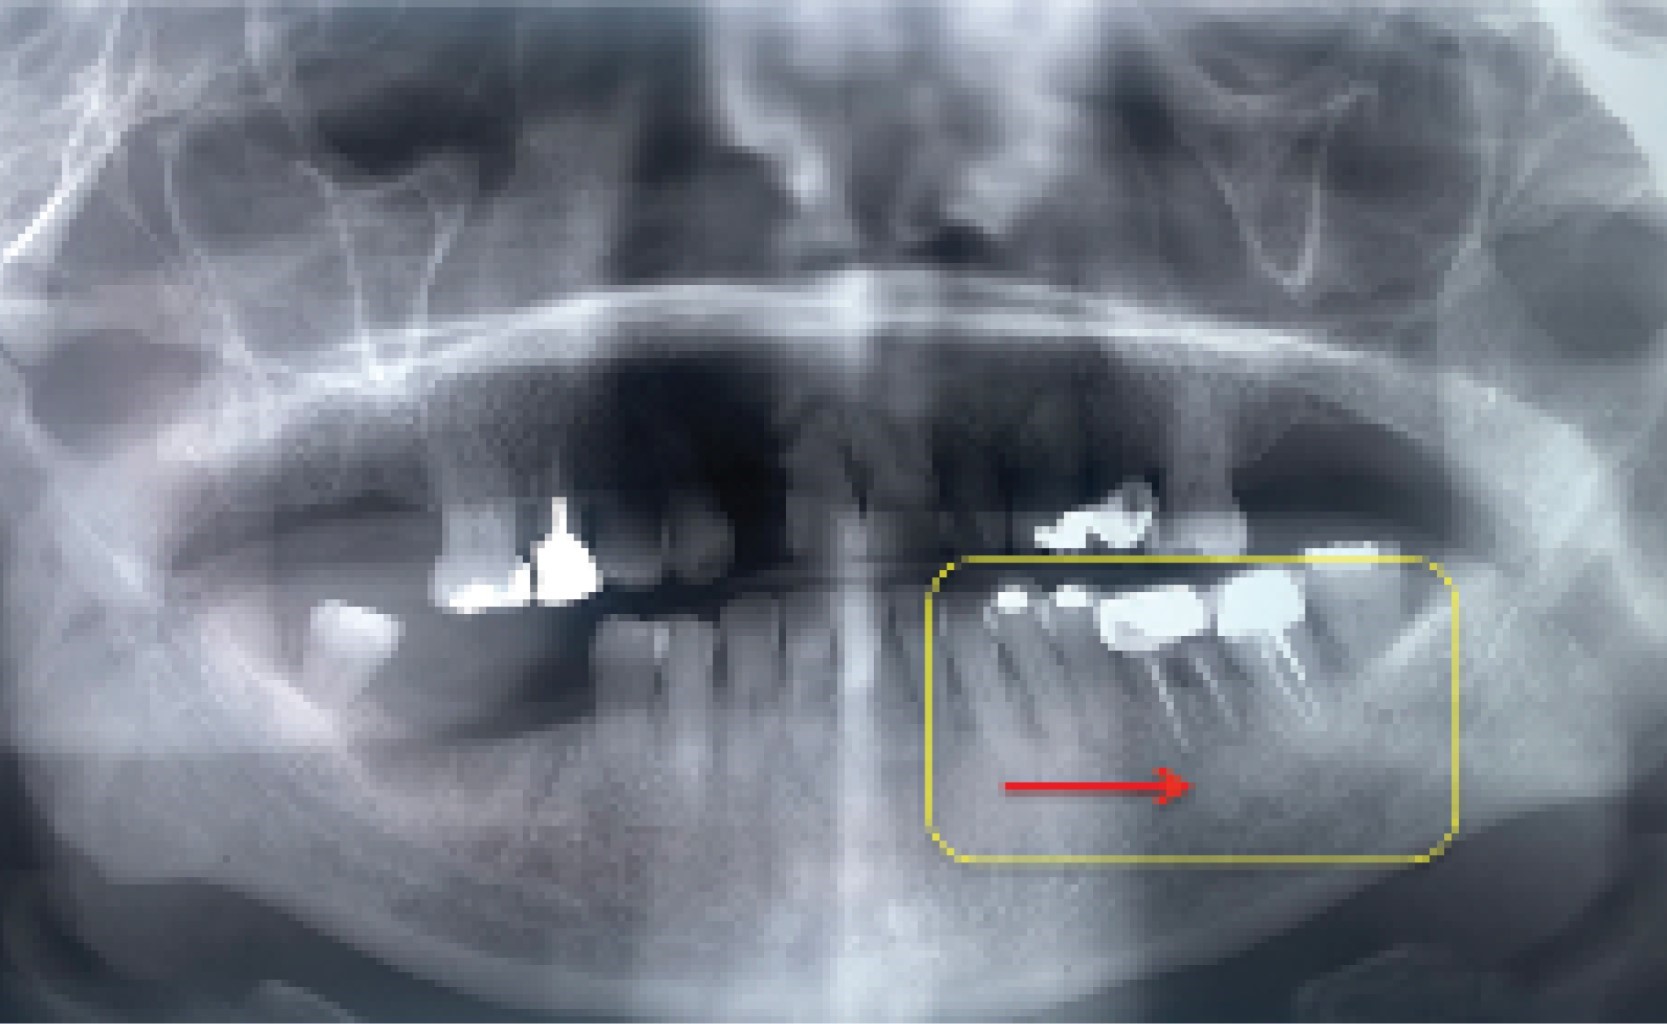

Paciente femenino de 69 años de edad, quien acudió en abril de 2016 a consulta por presentar dolor en hemimandíbula izquierda secundario a curetaje periodontal abierto realizado tres semanas previo a su consulta. Como padecimientos importantes la paciente presentó carcinoma de mama izquierda en 2006 que se trató con resección quirúrgica y quimioterapia. Colocación de prótesis de cadera izquierda en 2009 y administración de ácido zoledrónico vía intravenosa cada dos meses hasta la actualidad. A la exploración física inicial se encontró aumento de volumen en región de cuerpo mandibular izquierdo, movilidad dental grado II-III en órganos dentarios 36 y 37, encía de la región mencionada eritematosa y presencia de exudado serohemático a la compresión de la región. Se decidió manejo inicial solicitando radiografía panorámica (Figura 1), se administró amoxicilina-ácido clavulánico 875/125 mg cada 12 horas durante tres meses, clorhexidina, se recomendó higiene oral exhaustiva, ibuprofeno para control del dolor, endodoncia del OD 36 y la extracción de los molares involucrados de oclusión. La paciente acudió inicialmente tres veces por semana a lavados y control y posteriormente, dos veces por semana. Presentó buena evolución hasta febrero de 2017 cuando se presentó con fístula intraoral con exudado purulento y secuestro óseo a nivel del OD 36 además de parestesia labial izquierda. Se decidió iniciar clindamicina 300 mg vía oral cada ocho horas, la cual no toleró de manera adecuada, por lo que a los 10 días se cambió por moxifloxacino 400 mg vía oral cada 24 horas durante un mes. Se le colocó ácido zoledrónico por indicación oncológica en noviembre de 2017. Se continuó con manejo conservador, antibióticos sistémicos, colutorios y clorhexidina tópica, analgésicos en caso de dolor, higiene oral estricta y consultas a lavado tres veces por semana durante un año. En septiembre de 2018 continuó con múltiples fístulas intraorales vestibulares y hueso expuesto en diversos puntos del cuadrante III. Se solicitó tomografía en la cual se observó osteólisis en hemimandíbula derecha sector posterior y hueso de características anormales en cuerpo mandibular izquierdo. En este punto se decidió no retirar órganos dentarios 36 y 37 hasta que tuvieran tejido de granulación en su porción apical y la extracción fuera, en medida de lo posible, sin exposición ósea. En octubre de 2019 se realizó extracción de 36 sin complicaciones y a la semana acudió con exudado purulento fétido y hueso necrótico en vestibular. Se realizaron curaciones diarias con buena evolución y se dieron citas dos veces por semana. En mayo de 2019 acudió con absceso submandibular izquierdo, que se drenó de manera extraoral, presentando 20 cm3 aproximadamente de exudado purulento. Se agregó metronidazol 500 mg vía oral cada 8 horas a esquema antibiótico y acudió a curaciones diarias sin complicaciones, la herida cicatrizó de manera espontánea. Se solicitó nueva radiografía panorámica en la que se observó franca lisis en cuadrante tres abarcando porción de la basal mandibular (Figura 2). En julio de 2019 se realizó extracción atraumática de 37 con adecuada evolución. En septiembre de 2019 continuó con hueso expuesto. Cabe resaltar que se tomaron cultivos de las fístulas y se aislaron Streptococcus anginosus y biopsias que reportaron hueso necrótico por el Servicio de Patología.

Figura 2